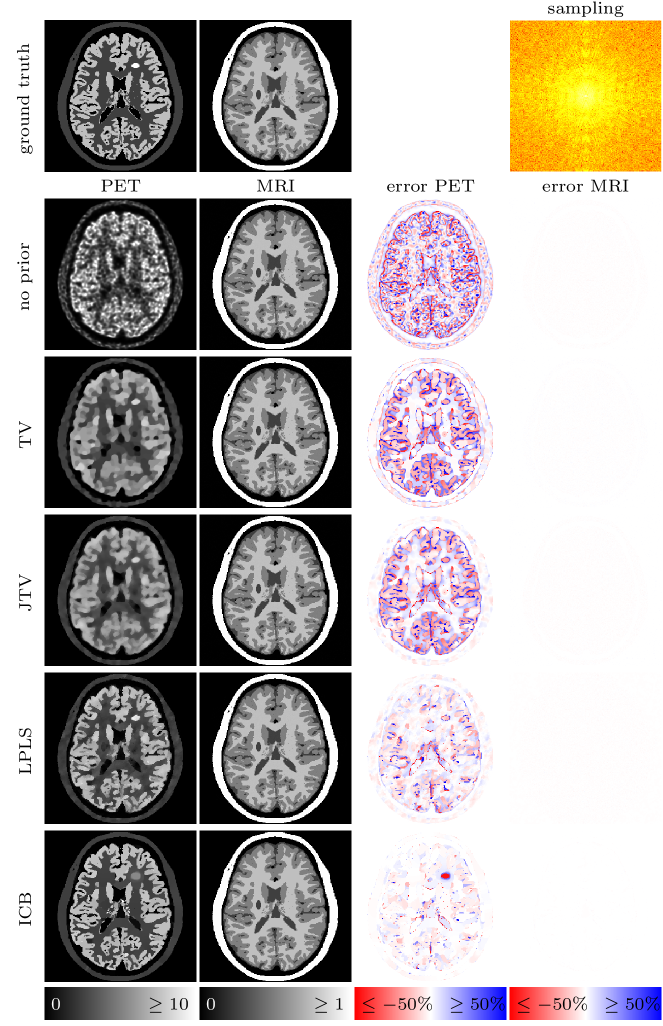

In case of MRI we use undersampled -space data, meaning that we sample the Fourier space only at a few frequencies specified by different geometries. For the sake of simplicity, the MRI operator hence consists of a 2-dimensional Fourier transform followed by a projection onto the geometric pattern of the corresponding sampling (cf. [20] . Note that we do not use a non-uniform Fourier transform since the chosen frequencies are still located on a Cartesian grid. However, the idea and method do not change for non-Cartesian methods. Eventually, Gaussian noise with an energy of approximately five percent of the total energy of the data set is added. We show four different types of undersampling in this work, which can be seen in Figure 6. The samplings introduce different types of artifacts and hence serve different purposes for the joint reconstruction setting which we elaborate on alongside with the results below.

![]() |

| (a) Full: | (b) Half: | (c) Spokes: | (d) Spiral: |

4.4 Results

Figures 9 to 12 show the results for four different MRI samplings and different types of regularization. The left two columns display the PET and MRI reconstructions, where all pictures are put onto the original scale of the ground truth, i.e. for PET and for MRI. If the reconstructions overestimate the image values beyond that scale, the corresponding pixels are set to the maximum value (note that an underestimation below zero is impossible due to the positivity constraint). The effective over- or underestimation of image values with respect to the ground truth can be assessed from the difference images on the right-hand side of the figures. Note that due to the missing weighting between gradients for JTV and LPLS, we had to rescale the PET data by a factor of in order to approximately provide the same range of image intensities for both PET and MRI. The results have then eventually been rescaled to their original range. We mention that due to the nonlinearity of the methods this may result in a slight change of quantitative values.

4.4.1 Full sampling

For a full sampling, already a separate reconstruction provides a visually perfect MR image, which remains the case for all priors. Here, the weighting for ICB is chosen such that the PET image does not influence the reconstruction of the MR image () and the procedure is similar to a PET reconstruction with an (evolving) anatomical prior. The MR reconstruction performed in parallel hence corresponds to a single channel BTV reconstruction. The quality of the PET image varies greatly. Without any prior, the PET image shows the typical noisy and blurry appearance of reconstructions from noisy Poisson data. The TV prior removes the noise, but highly oversmoothes the image. The first joint reconstruction method, JTV, is able to transfer some part of the sharp structures of the MR image to the PET image and increases its quality. However, the result remains too smooth. LPLS and ICB both show a substantial improvement of the image quality in terms of sharp edges and noise reduction. However, LPLS still features some remaining noise, and the lesion in the MRI not present in PET has been partly transferred. The result for ICB seems visually perfect on the shared structures of the image which can as well be assessed from the difference image. The only drawback is the smoothing of the hot lesion only present in the PET image, while we however observe that the MRI lesion has not been transferred. The observations are as well confirmed by the SSIM values in Table 1.

4.4.2 Half sampling

Sampling every second line of the k-space introduces a ghosting artifact into the MR image. JTV and LPLS show a similar performance in removing some parts of these artifacts from the MRI, while LPLS as well shows a clear improvement of the PET image. However, both lesions are again artificially shared between the images. The ICB results contain the least artifacts for MRI and the highest improvement for the PET image, where however again the hot lesion is attenuated. We as well find a slight transfer of the lesion from the MR image into the PET image, whereas the lesion from PET is not transferred to the MR image.

4.4.3 Spokes sampling

The situation for a spokes sampling is almost identical to a full MR sampling. Since already a TV prior removes the resulting grain artifacts, we again choose the weighting for ICB such that the PET image does not influence the MR image (). Interestingly, JTV and LPLS decrease the quality of the MR image, both visually and in terms of SSIM, by re-introducing some part of the noise. However, the PET image still benefits significantly from the influence of the MRI. ICB again shows the best performance for PET, sharpening the edges and restoring the quantitative values, where we again observe the attenuation of the hot lesion and transfer of the MR lesion.

4.4.4 Spiral sampling

For a spiral sampling, we again expect a mutual benefit for both modalities, since the sampling introduces some circular artifacts. Surprisingly, JTV delivers the best result in terms of SSIM, which however look too smooth. Visually the results for LPLS convince the most, both for PET and MRI. The ICB result for PET is sharper and more accurate in terms of quantitative values, but appears a little too noisy, which can as well be caused by the influence of the undersampled MR image.